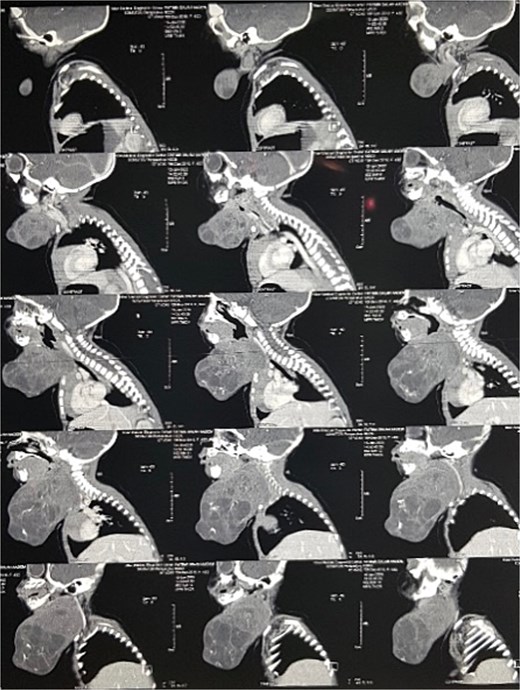

On examination of the neck, the patient has a large anterior neck mass measuring 15 × 20 cm in diameter, with apparent lobulations and a cystic nature. The face appeared edematous, and the trachea was not palpable, with stridor evident on auscultation (Fig. 1). A soft tissue ultrasound revealed a cystic swelling that is not separable from the adjacent thyroid gland. A subsequent CT scan of the neck showed highly lobulated soft tissue that enhances with calcifications (Fig. 2).

Perioperative picture of the patient showing the extent of facial deformity caused by the tumor.